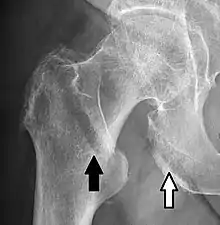

• Hip joint: AP and Lateral.[15]

• The Lauenstein projection a form of examination of the hip joint emphasizing the relationship of the femur to the acetabulum. The knee of the affected leg is flexed, and the thigh is drawn up to nearly a right angle. This is also called the frog-leg position.

Applications include X-ray of hip dysplasia.